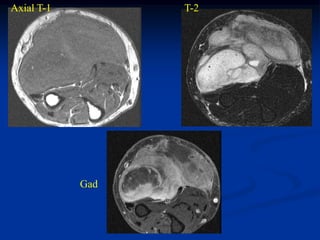

Case #259.2                   MFH with skip lesions

64 year male with painful soft tissue mass in thigh for 6 mos

Cor STIR   Ant STIR   Gad

Axial T-2   Lower T-2

Lower Gad

Sag Gad   Gad

Case #259.2 MFH with skip lesions 64 year male with painful soft tissue mass in thigh for 6 mos

• 147.

• 148.

Axial T-2 Lower T-2 Lower Gad